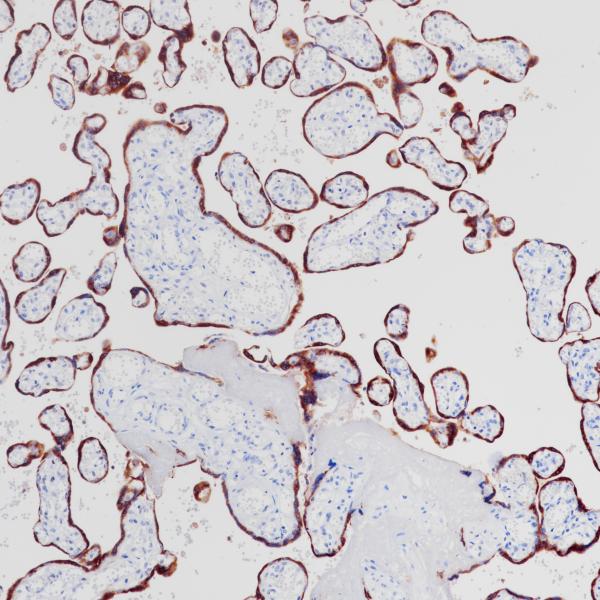

HLA-G

BP6247